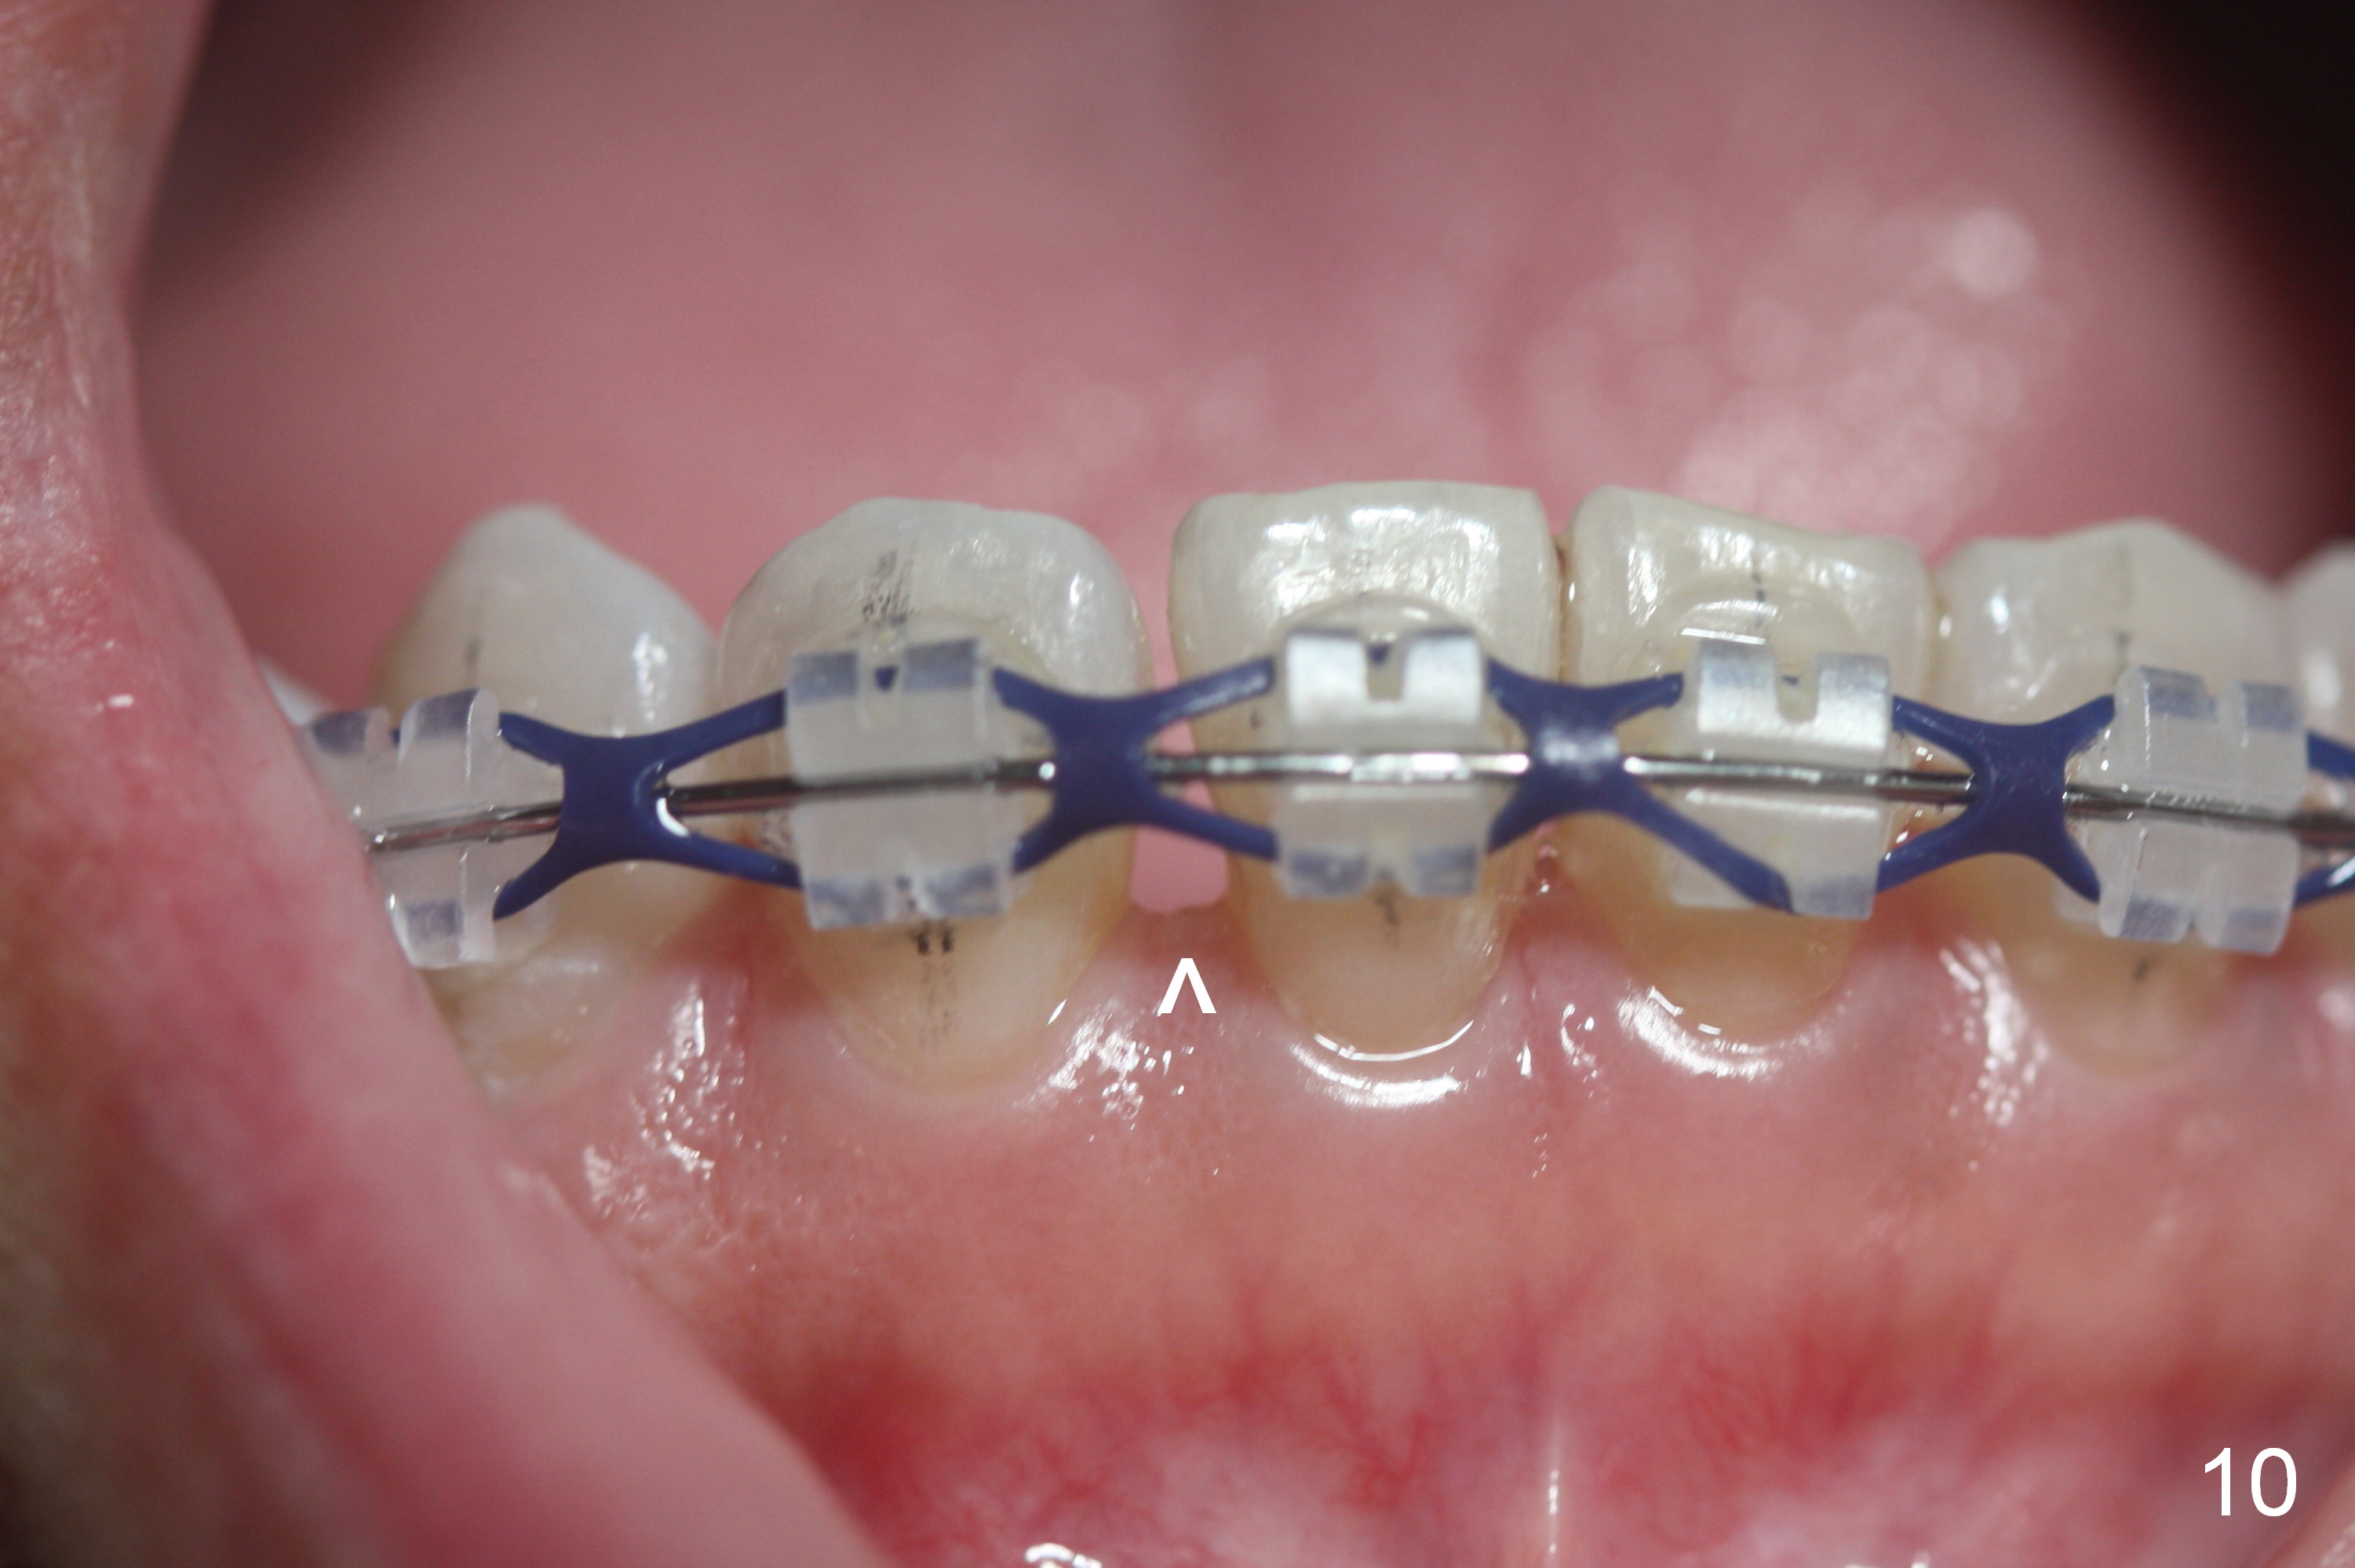

Four weeks of using open coil spring between #29 and 31, these teeth seem to have rotated (Fig.8,9 curved arrows). After placing a longer spring and the same arch wire, power chains are installed to close the anterior diastema (Fig.10 ^). The patient notes the divergence between #20 and 21 (Fig.11). To correct the latter, either place #20 bracket more distal (Fig.11 *) or place power chains between these teeth only. To facilitate #31 distalization (Fig.13), place lingual buttons (Fig.12 red) in the mesial surface of #31 and the distal of #2 with an elastic between the buttons.